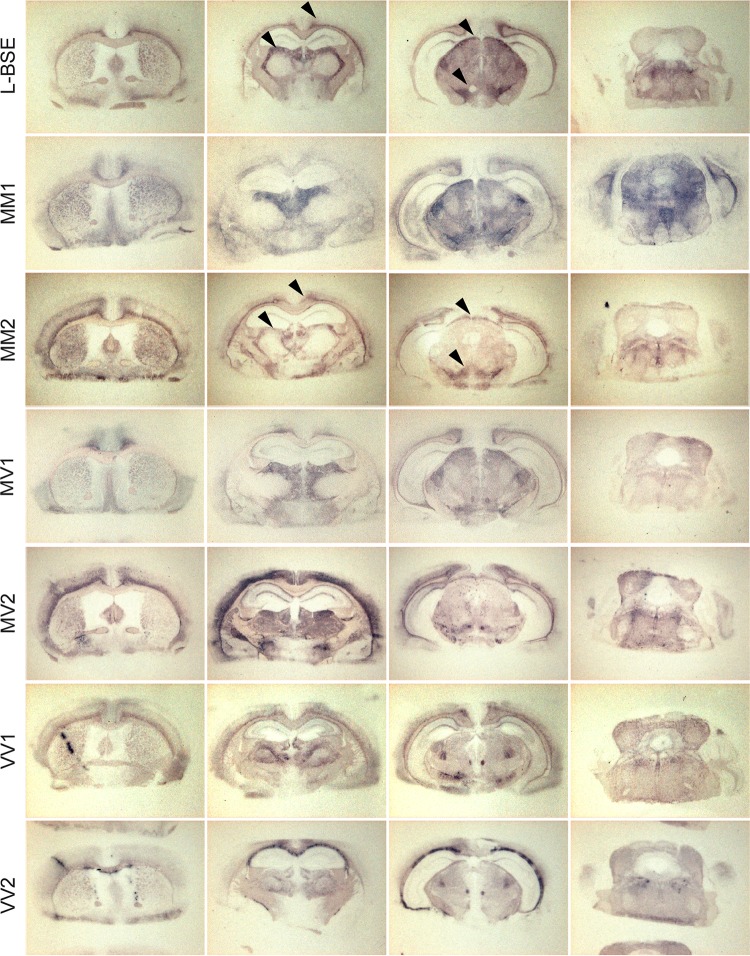

The strain-specified (2) neuroanatomical distribution of PrPres deposits in the brain was studied by histoblotting. L-BSE exhibited a PrPres deposition pattern in the tg650 mouse brain that was superimposable only on MM2-sCJD prions (Fig. 2). PrPres deposition was prominent in the dorsal and habenular thalamic nuclei, in the optic tract, in the cingulum, in the external capsule, in the lateral hypothalamic area, and in the trigeminal nuclei of tg650 mouse brains (Fig. 2) (24). Variations in PrPres distribution patterns and in the nature of the deposits among the sCJD types allowed further segregation into five distinct strain types: MM1/MV1, MM2, MV2, VV1, and VV2. In particular, there were granular, plaque-like deposits specifically present in the corpus callosum of VV2-inoculated mice, whereas MV2 deposits were thinner and mostly located in the thalamus and in the cortical areas (Fig. 2). The VV2 deposits were thioflavin-S positive, indicating an amyloid fibril organization (Fig. 3).

FIG 2.

Neuroanatomical distribution of PrPres in human PrP transgenic mice challenged with L-type BSE prions or human CJD subtypes. Representative histoblots in four antero-posterior sections showing the deposition of disease-specific PrPres deposits in the brains of tg650 mice infected with L-BSE prions or sCJD prions, as indicated. Arrowheads point to similar PrPres deposition patterns after challenge with L-BSE and MM2-sCJD prions. Note the difference in the appearance of the PrPres deposits of the VV2 and MV2 sCJD subtypes. Analysis was performed at the 3rd passage. Histoblots were probed with 3F4 anti-PrP monoclonal antibody.